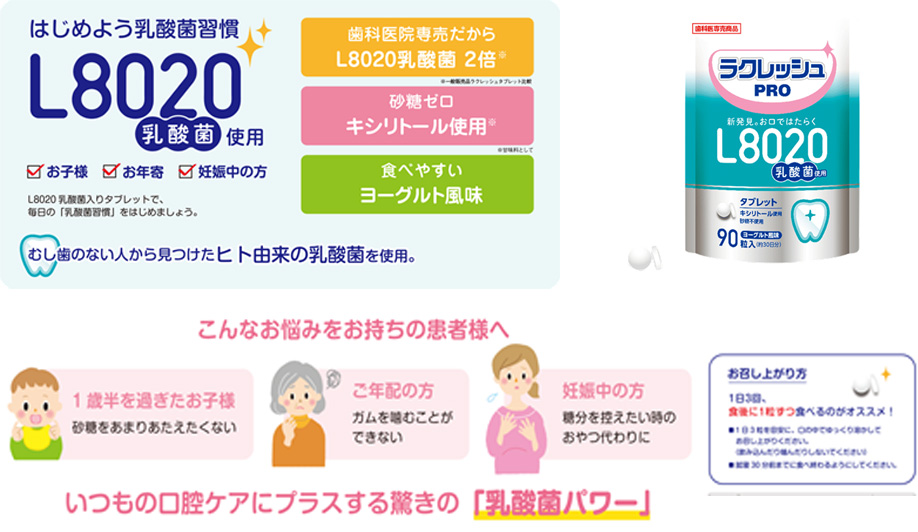

乳酸菌Lactic acid bacteria

L8020乳酸菌とは

L8020乳酸菌とは歯周病、むし歯になったことのない健康な子どもの口の中から発見されたヒト由来の乳酸菌です。歯周病菌・むし歯菌の発育を阻止する、制菌効果のある乳酸菌の一種で、ヒトの口腔内から5種類の歯周病菌とむし歯菌・カンジダ菌を効果的に抑制し、口腔内環境を健康に保ちます。

バクテリアセラピーの3大特徴

①効果持続性

- ・善玉菌を増やして体質の改善をめざします。

- ・体内菌バランスを整え、悪玉菌を抑制します。

②耐性フリー

- ・悪玉菌に善玉菌を対抗する方法なので、薬のよう に悪玉菌が善玉菌に対して耐性を持つことが少な いと考えられます。

③安全性

- ・ヒト由来の善玉菌なので体に定着しやすい。

- ・お子様からご年配の方、妊娠中の方まで安心して摂取できます。